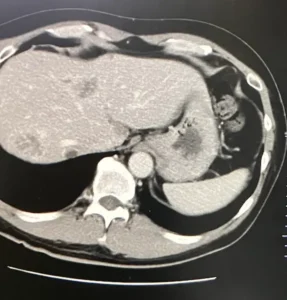

CT検査の結果は良好でした。 肝臓に転移したがんが、目に見えて小さくなっていたのです。

(腫瘍マーカー:178)

3か月おきのCT検査です。肝臓に転移したがんはさらに小さくなっていました。

(腫瘍マーカー16)

それを証明するかのように腫瘍マーカーも下がっていました。